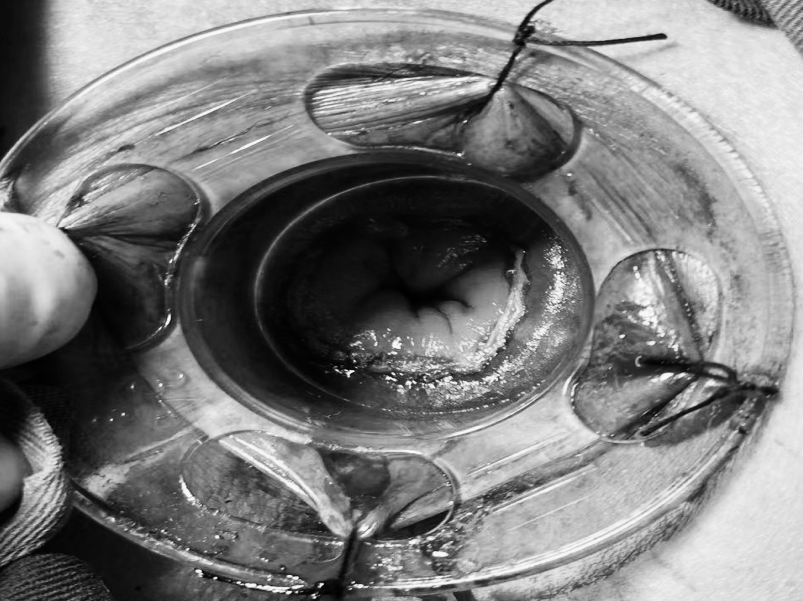

一名女性患者长期受到下腹部坠胀、排便不适等症状困扰,近期发现盆腔内存在肿物,严重影响其生活质量,为寻求进一步诊治,她前往贵州航天医院普外科就诊,经核磁共振(MRI)检查提示:盆腔内直肠与骶骨之间有一个“骶前囊肿”。由于该囊肿位置深,且与周围重要的神经和血管关系密切,若采用传统手术不仅创伤大,还伴随一定的风险。 面对这一棘手难题,普外科立即组织了麻醉科、医学影像科、妇科、重症医学科在内的多学科专家会诊(MDT)。经专家团队详细评估,与患者及家属充分沟通后,为患者制定并成功实施了“腹腔镜下骶前囊肿切除术”。术后恢复良好,不久便康复出院。 【疾病科普|什么是骶前囊肿?】 骶前囊肿,可以理解为生长在骨盆最深处、直肠后方的一个囊性肿物。由于它“躲藏”的位置非常特殊,四周紧邻着控制排便和感觉的重要神经与血管,因此被视为盆腔外科手术中的一个难点。 它可能带来哪些影响? 1.随着囊肿逐渐增大,可能会压迫直肠,引起排便困难或坠胀感。 2.压迫骶神经,可能导致腰骶部或会阴区的酸胀、疼痛。 3.囊肿本身也可能发生感染,形成脓肿,加重不适。 【技术介绍|腹腔镜下骶前囊肿切除术】 对于骶前囊肿这类较深的病灶,腹腔镜下骶前囊肿切除术提供了一种更为微创、便于操作的解决方案。 它是如何进行的? 医生仅通过腹部几个约0.5-1厘米的小孔,其中一个孔放入带高清摄像头的腹腔镜,将盆腔内的景象放大并清晰地投射到屏幕上,如同给了医生一双进入体内的“眼睛”。其他几个小孔则伸入细长的专用手术器械。医生看着屏幕,遥控这些器械,在清晰的视野下精细地分离并完整切除囊肿。 腹腔镜微创手术的特点包括: ▶创伤较小:避免了传统手术的长切口,体表疤痕小。 ▶视野清晰:放大后的图像让医生能更清楚地分辨囊肿与周围重要结构。 ▶操作精准:有助于更完整地切除囊肿,并尽力保护盆腔神经功能。 ▶恢复较快:因手术创伤小,患者术后疼痛感更轻,下床活动早,住院时间也可能缩短。 注:本文旨在进行健康科普,分享医疗案例与科普知识,不能替代任何专业的医疗建议。如有任何健康问题,请务必及时咨询并遵从专业医生的诊疗意见。 贵州航天医院普外科专家简介 高大勇 普外科(肛肠外科)学科带头人、名誉主任,主任医师、教授 临床擅长:对中西医结合诊治肛肠学科各种常见病、多发病及疑难杂症等具有丰富的临床经验。 原遵义市第一人民医院(遵义医科大学第三附属医院)、遵义市中医院肛肠科主任。中华中医药学会肛肠分会常委,全国中医肛肠学科名专家,中国健康促进与教育协会肛肠分会常委,中国康复医学会肛肠疾病康复专业委员会常委,中国民间中医医药研究开发协会肛肠分会副秘书长,中国医师协会中西医结合肛肠医师专业委员会常委,国家二级心理咨询师,贵州省第一批中医名医工作指导老师,遵义市名中医,遵义市肛肠学会会长,遵义市肛肠质控中心名誉主任,遵义市中西医结合学会名誉会长,遵义市健康科普专家,原贵州省中西医结合学会肛肠分会副主任委员、贵州省中医肛肠质控中心副主任、遵义市医学会医疗鉴定委员会专家、遵义市卫生系列高级评委。发表论文30余篇,主编和参编医学著作5本,主持省级科研课题2项、市级科研课题2项、院级科研课题1项。 梁 跃 普外科党支部书记、主任,主任医师 临床擅长:对普外科各类肿瘤手术具有丰富的临床经验。 毕业于遵义医学院,遵义市医学会小儿外科学分会常务委员,遵义市肛肠协会理事,遵义市医学会核医学分会(第二届)委员会委员;荣获第三期“黔医人才计划”优秀学员称号;主持市级课题1项,完成省级课题1项,在国内各类刊物上发表论文10余篇。 钱科洪 民盟盟员,普外科副主任医师 临床擅长:从事普外科临床工作30余年,对各类普外科疾病的诊治、乳腺、甲状腺、胃十二指肠、结直肠等疾病及疑难杂症具有丰富的临床经验。 毕业于遵义医学院临床医疗系,2009年前往中山大学附属第一医院微创外科进修学习,在国内各专业期刊发表论文数篇。 贵州航天医院普外科简介 基本情况 贵州航天医院普外科成立于1968年,前身属于原航天部O61基地3417医院外一科,1998年3417医院、3427医院合并后更名为普外科,下设胃肠外科、肛肠外科2个亚专业科室,拥有在全市较为先进的专科设备和技术,是中国疝病专科联盟单位,贵州医科大学附属医院胃肠外科专科联盟单位。开放床位40张,配备医护人员21人。 专科特色 普外科致力于胃肠及肛肠疾病的外科临床诊治及科研,以腹腔镜微创外科技术为本,形成以快速康复治疗胃肿瘤、结直肠肿瘤、小肠肿瘤、直肠脱垂、肥胖病、急腹症、各类疝、痔、瘘等专科特色,同时注重胃肠疾病尤其是结直肠恶性肿瘤的基础研究和临床转化研究,总体诊断和治疗水平在区域同级医院居于领先水平。 开展手术:腹腔镜下胃癌根治术,腹腔镜下袖状胃切除术,腹腔镜下胃肠道间质瘤切除术,腹腔镜下结、直肠癌根治术,胃癌、结直肠癌的精准治疗,腹腔镜下小儿疝气、成人疝修补术,腹腔镜下阑尾手术,内痔的硬化注射治疗及痔疮的微创治疗:ATH、PPH、TST,直肠脱垂的各种手术治疗,难治性伤口VSD技术,鼻胃肠管、肠梗阻导管置入术,肛肠术后间歇性导尿技术,并引进了中医适宜技术,也为各种化疗患者提供输液港安装,提高患者就医体验。 腹腔镜下腹股沟疝 无张力修补术 腹股沟疝里金斯坦 (Lichtenstein)手术 PPH微创术治疗环状混合痔 黏连性或炎性肠梗阻-肠梗阻导管 腹腔镜袖状胃切除 腹腔镜阑尾切除术 腹腔镜阑尾肿瘤切除术 腹腔镜下结肠癌根治术 诊疗范围 胃肿瘤、结直肠肿瘤、小肠肿瘤、肥胖症、各类急腹症、腹部外伤、腹壁疝、便秘、直肠脱垂、痔疮、肛瘘、肛裂等胃肠、肛肠外科疾病。 END